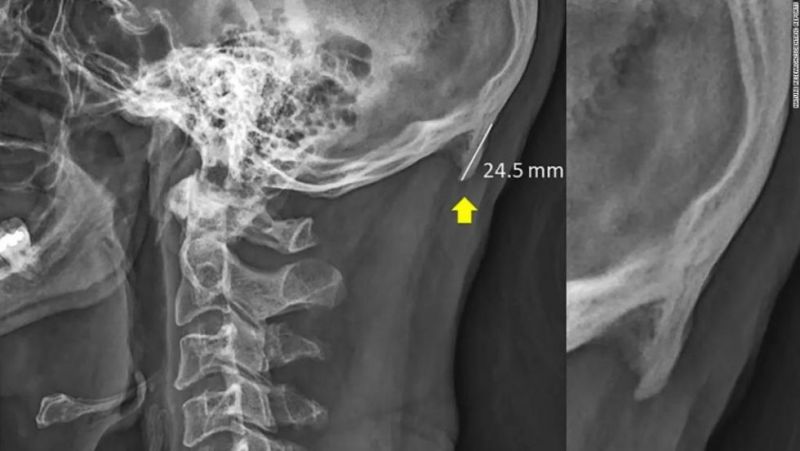

En su investigación, Shahar y Sayers dijeron que los jóvenes pueden estar desarrollando pequeños picos en forma de cuernos en la parte posterior de sus cráneos, posiblemente debido al cambio en el peso de nuestras cabezas desde la columna vertebral a los músculos de la parte posterior de nuestra cabeza y cuello. Esta característica anatómica se denomina protuberancia occipital externa o EOP, por sus siglas en inglés.

Para su primer estudio, los dos investigadores establecieron un umbral de 5 milímetros para registrar un EOP, y lo consideraron un EOP agrandado si superaba los 10 milímetros de longitud. Descubrieron que el 41% de los participantes, entre las edades de 18 a 30 años, tenían un EOP agrandado en sus cráneos.

Su segundo trabajo estudió un tamaño de muestra más grande de 1.200 rayos X para sujetos de 18 a 86 años de edad. El 33% de los sujetos tenían el crecimiento óseo, pero curiosamente, el crecimiento disminuyó con la edad.